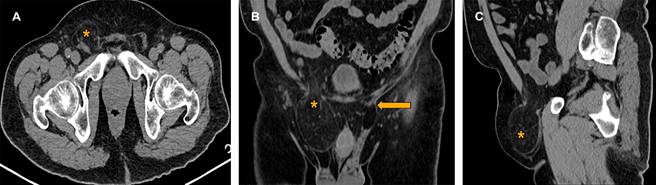

Se ingresaron un total de 292 pacientes, de los cuales, la mediana de edad fue 48.7 años (rango 36-60), del sexo masculino fueron 127 (43.5%) y del femenino 165 (56.5%). La media de IMC fue 29.6 ± 2.4. De acuerdo con la clasificación de IMC, los pacientes con sobrepeso fueron 166 (56.8%), con obesidad grado I, 93 (31.8%); obesidad grado II, 24 (8.2%) y obesidad grado III, 9 (3.1%). Confirmados de hernia inguinal (Figura 1) fueron un total de 117 (40.1%), de los cuales hernia inguinal indirecta (Figura 2) fueron 105 (36%) y directa fueron 12 (4.1%). La localización más frecuente fue izquierda 43 (14.7%), derecha 34 (11.6%), bilateral 40 (13.7%). El diagnóstico presuntivo habitualmente referido por lo cual se solicitó el estudio fue el dolor abdominal siendo 113 pacientes (38.7%) (Tabla 1).

Figura 1: Hernia inguinal bilateral. Tomografía computarizada en fase simple con reconstrucción multiplanar de la región pélvica en planos A) axial, B) coronal y C) sagital. En la que se muestra un anillo herniario inguinal con saco herniario de contenido graso epiploico de lado derecho(*). De la misma forma, se observa pequeño anillo herniario inguinal de contenido graso de lado izquierdo (←).